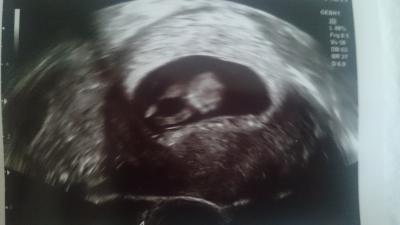

Das 2 Bild mit ganzem Körper :)

Bild zu